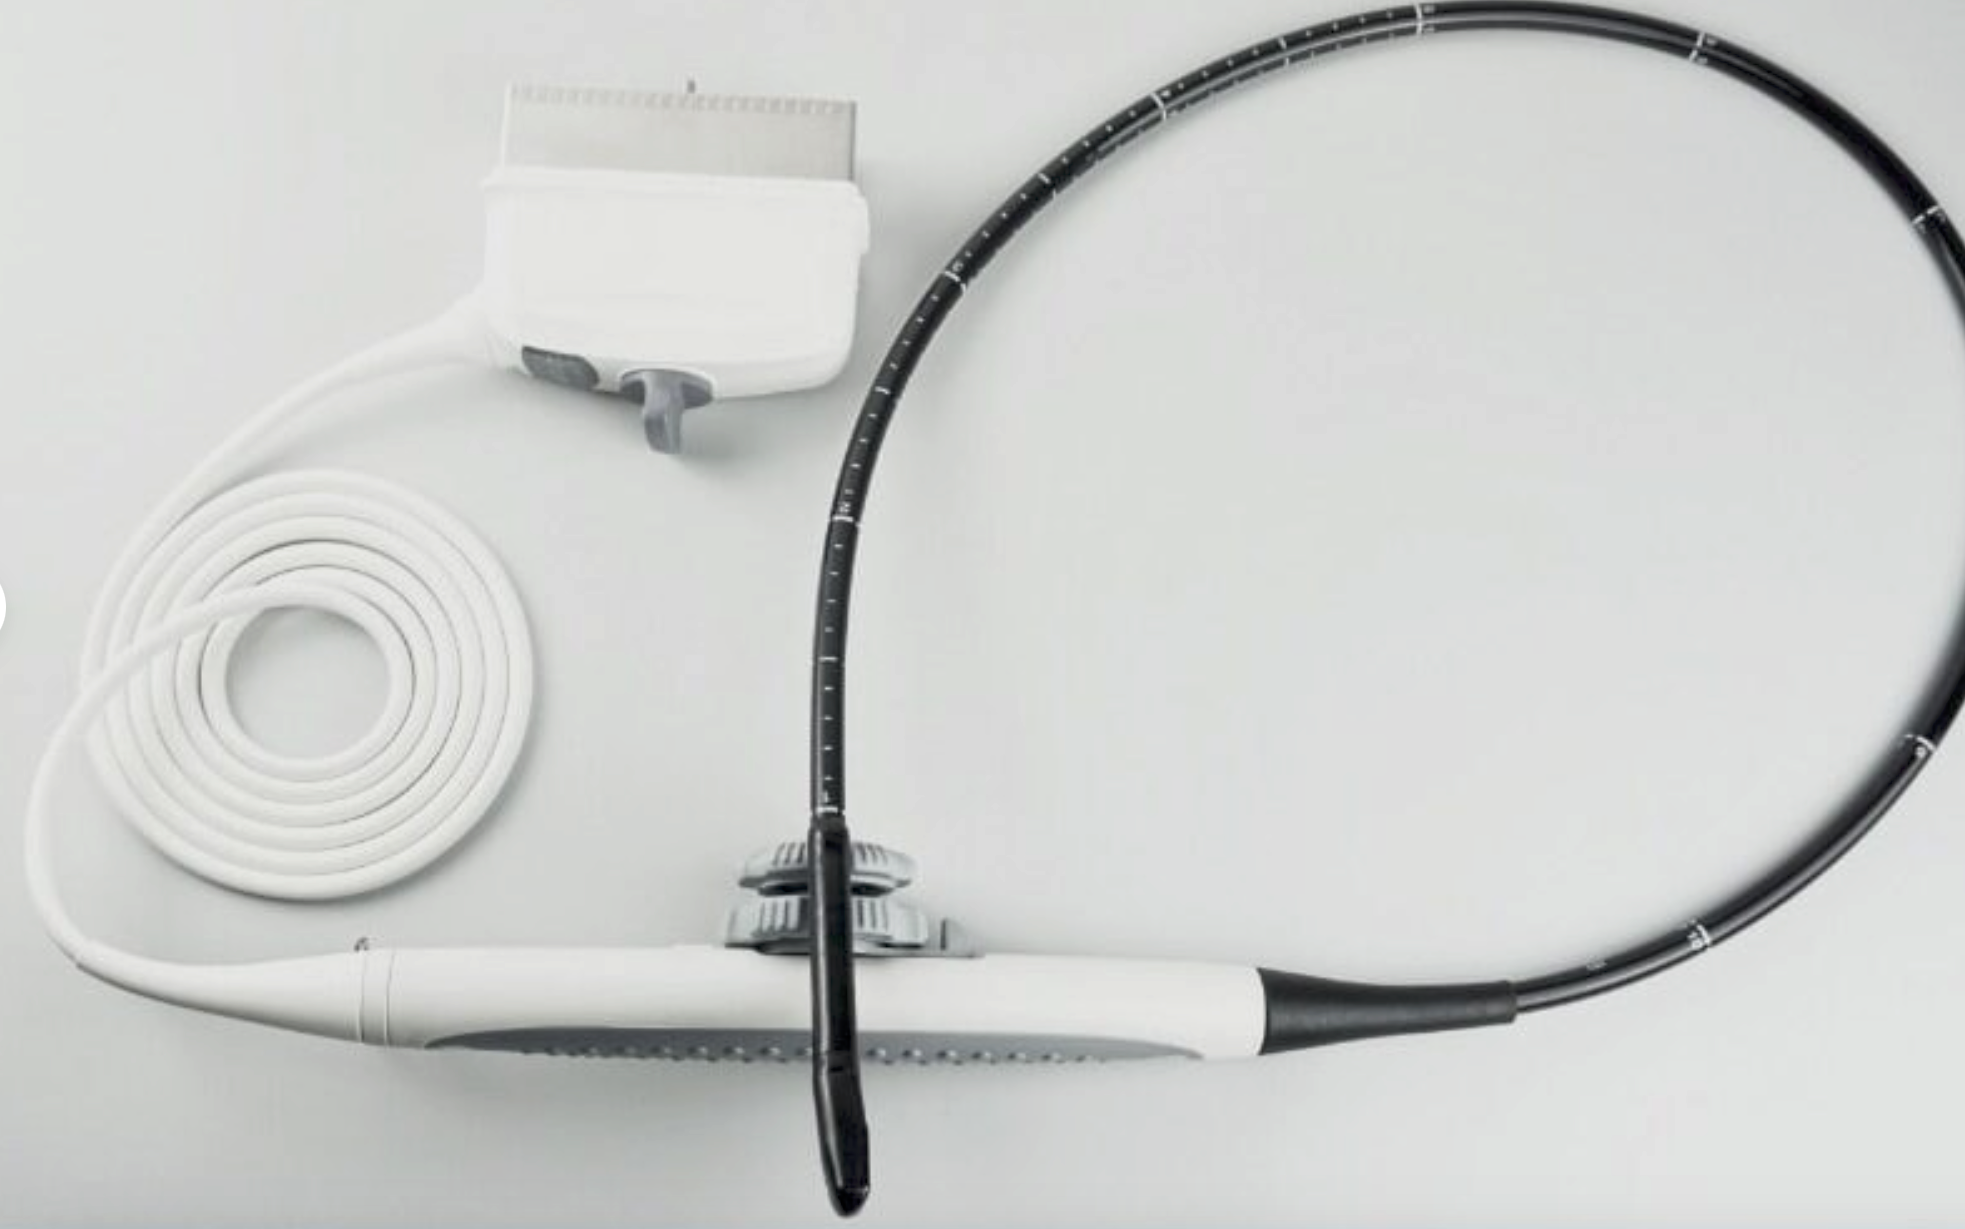

The CE Digital Laptop Ultrasound Machine offers outstanding imaging capabilities that are essential for modern diagnostic practices. It features a 6.5MHz Transvaginal probe that provides high-resolution images, enabling healthcare professionals to visualize internal structures with great clarity. This machine is designed to help in various examinations, ensuring better accuracy and improved patient care.